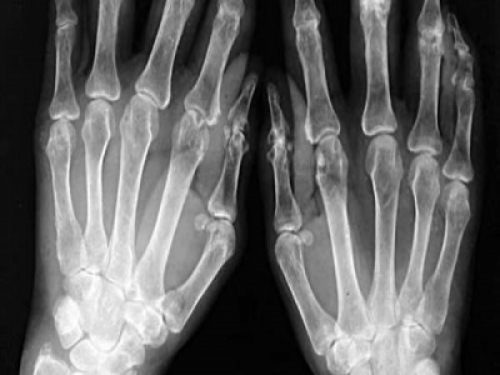

X線表現為:

早期:肘關節周圍組織腫脹如梭形,關節間隙因積液而增寬,骨質脫鈣、稀疏,肌腱、韌帶附著處出現少數羽毛狀骨膜增生和層狀骨膜反應。

晚期:關節軟骨破壞,關節面不規則,關節間隙變窄。關節軟骨下骨質出現細小囊狀骨質破壞,肱尺關節骨面密度升高,並且有增生。肘關節增粗,可有肘內翻或者肘外翻畸形。部分病人可有肘關節纖維性強直或者骨性強直。